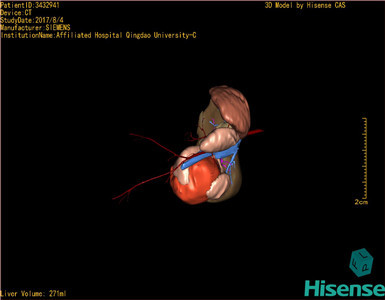

术前三维重建及手术方案设计:

将0.625mm双源薄层CT资料的静脉期和动脉期Dicom格式文件导入海信CAS系统。

通过调节窗宽窗位调整CT序号,对肿瘤,肝实质,胆囊,下腔静脉,肿瘤,肝动脉、门静脉及肝静脉等进行三维重建;系统自动计算肿瘤体积和肝脏体积。

模拟手术操作,自动计算切除肿瘤体积。肝脏体积为271ml,通过术前模拟手术,精准判断手术可行性。

术前三维重建:

重建图片